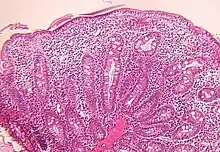

Small bowel

Microscopic examination of a biopsy of the small bowel in these patients shows villous atrophy with low or no mononuclear cell infiltration of the lamina propria nor specific abnormalities involving the epithelium. The amount of villous atrophy does not explain the severity of the diarrhea.